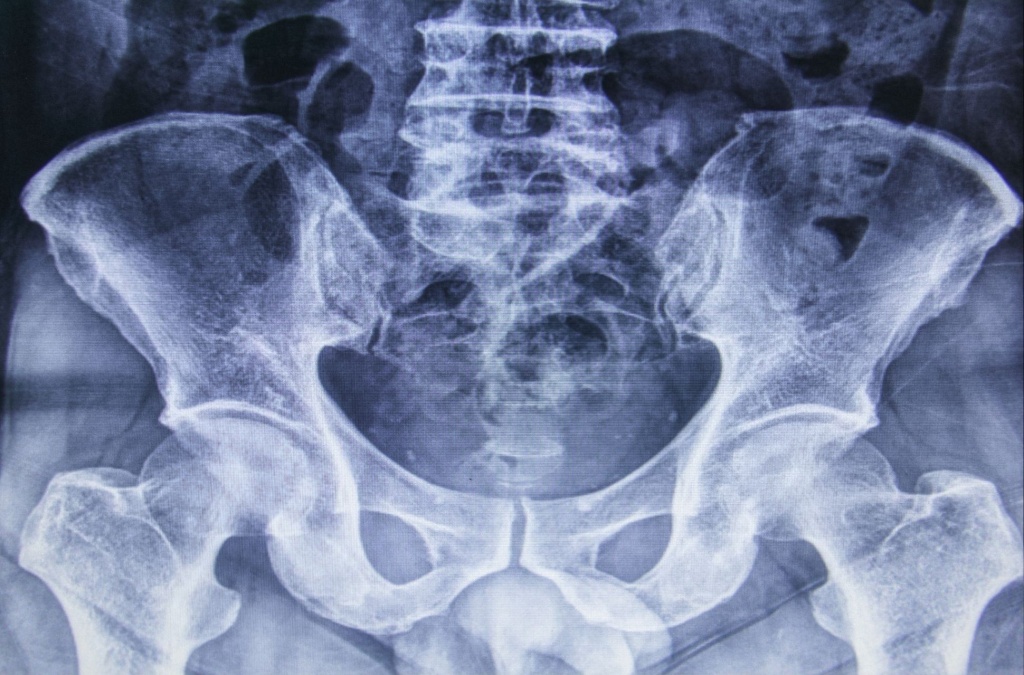

Таз – це основа руху. Те, на чому тримається хребет, через що передається навантаження на ноги, що забезпечує рівновагу тіла. Коли в цій зоні з’являється біль, асиметрія або відчуття нестабільності, це майже завжди впливає на ходу, поставу і навіть загальне самопочуття.

Рентгенографія тазу – інформативне дослідження, яке дозволяє оцінити стан тазових кісток і кульшових суглобів, побачити структурні зміни та визначити причину болю або обмеження руху.

Рентген таза часто використовується як базове дослідження перед подальшим лікуванням або додатковою діагностикою.